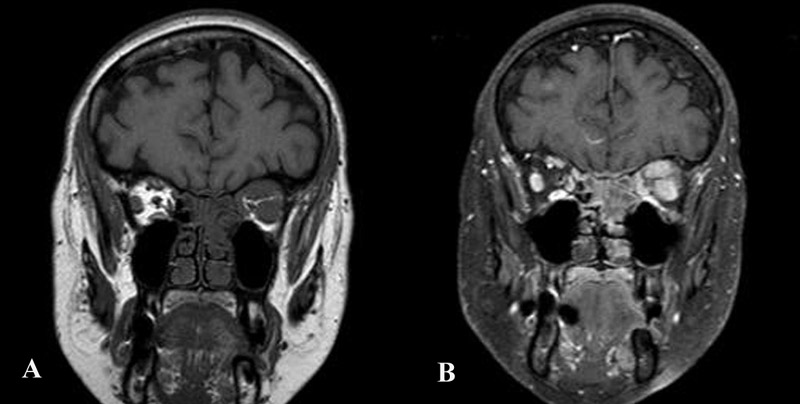

En este grupo se incluyen las metástasis orbitarias vía hematógena. Sólo representan el 1.5-3.3% de la patología orbitaria, sin embargo, hasta el 25% de las metástasis orbitarias pueden ser la primera manifestación del cáncer primario. El intervalo medio de aparición tras el diagnóstico del primario de es 6 años, y de 8 meses cuando se ha realizado es diagnóstico previo de otras metástasis sistémicas. Globalmente éstas suelen ser más prevalentes en mujeres que en hombres, con una proporción 2:1 y la afectación orbitaria unilateral. La clínica inicial varía según la localización y el tipo de crecimiento de la masa, la más habitual es dolor, proptosis, oftalmoplejía precoz y destrucción ósea. Los tumores que más frecuentemente metastatizan en la órbita durante la infancia son el neuroblastoma y las leucemias linfoblásticas agudas. En los adultos, el carcinoma de mama es el más frecuente en las mujeres, y en los hombres el de pulmón. Hasta en un 10% de las metástasis orbitarias no es posible detectar el tumor primario. Radiológicamente pueden adoptar mútiples patrones: a) masa de partes blandas localizadas o infiltrantes (unilaterales o bilaterales); b) afectación difusa de la musculatura extrínseca ocular; c) masa en ápex orbitario con extensión al seno cavernoso; d) lesiones preseptales infiltrantes; e) masas líticas localizadas principalmente en el ala mayor del esfenoides (

Figura 6).

Figura 6. Metástasis tumor de mama. RM orbitaria en plano coronal. A) Secuencia T1SE en la que se aprecia un engrosamiento de la musculatura extrínseca ocular de la órbita izquierda. B) Secuencia T1SPIR post-gadolinio. La musculatura extrínseca afecta muestra un marcado realce tras la administración de contraste endovenoso.